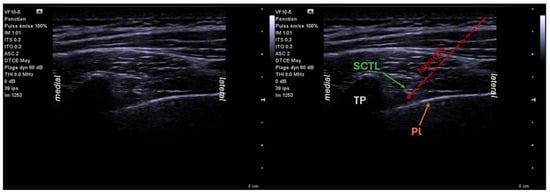

6.4. Serratus Block